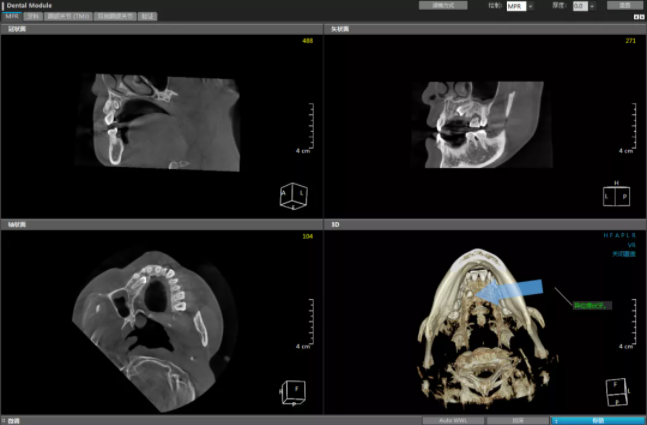

近日,29岁的小美因为先天性牙齿缺失一颗,来到娄星区人民医院(娄星区妇幼保健院)口腔科门诊咨询种植牙情况,在口腔CT检查的3D影像图片上,她看到了惊人的一幕,原来“缺失”的那颗牙跑到了上颚,呈现“葛优躺”姿态。小美急忙询问医师该怎么办,口腔科龙晓明主任告诉她这就是那颗“缺位”的牙齿——异位埋伏牙。

“所谓埋伏牙,即牙齿萌出期已过而仍在颌骨组织中未能萌出的牙齿。简单点说,就是你那颗缺位的牙齿没有在正常的位置萌出,而在上腭颌骨内游走,由于位置特殊,影响矫正和种植,这种情况下需要将它拔除。”